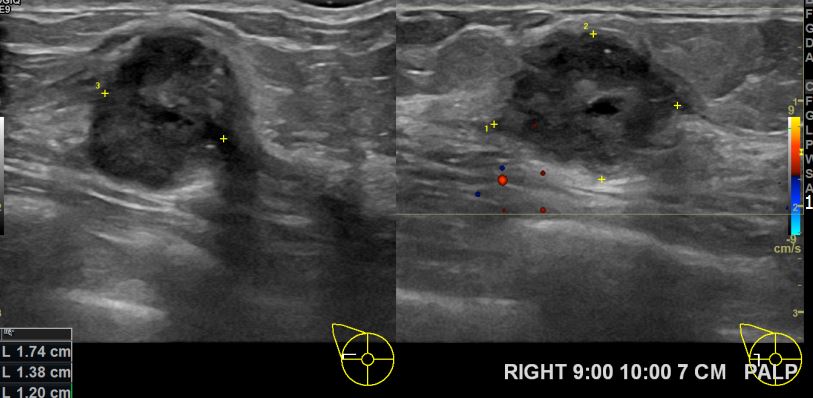

아산유외과 개원후 597번째 유방암 진단

상기환자 외부검사상 이상소견으로 내원하신 50대 여성분으로 우측유방 조직검사시행후

유방암 진단되었읍니다.빠른쾌유 바랍니다.